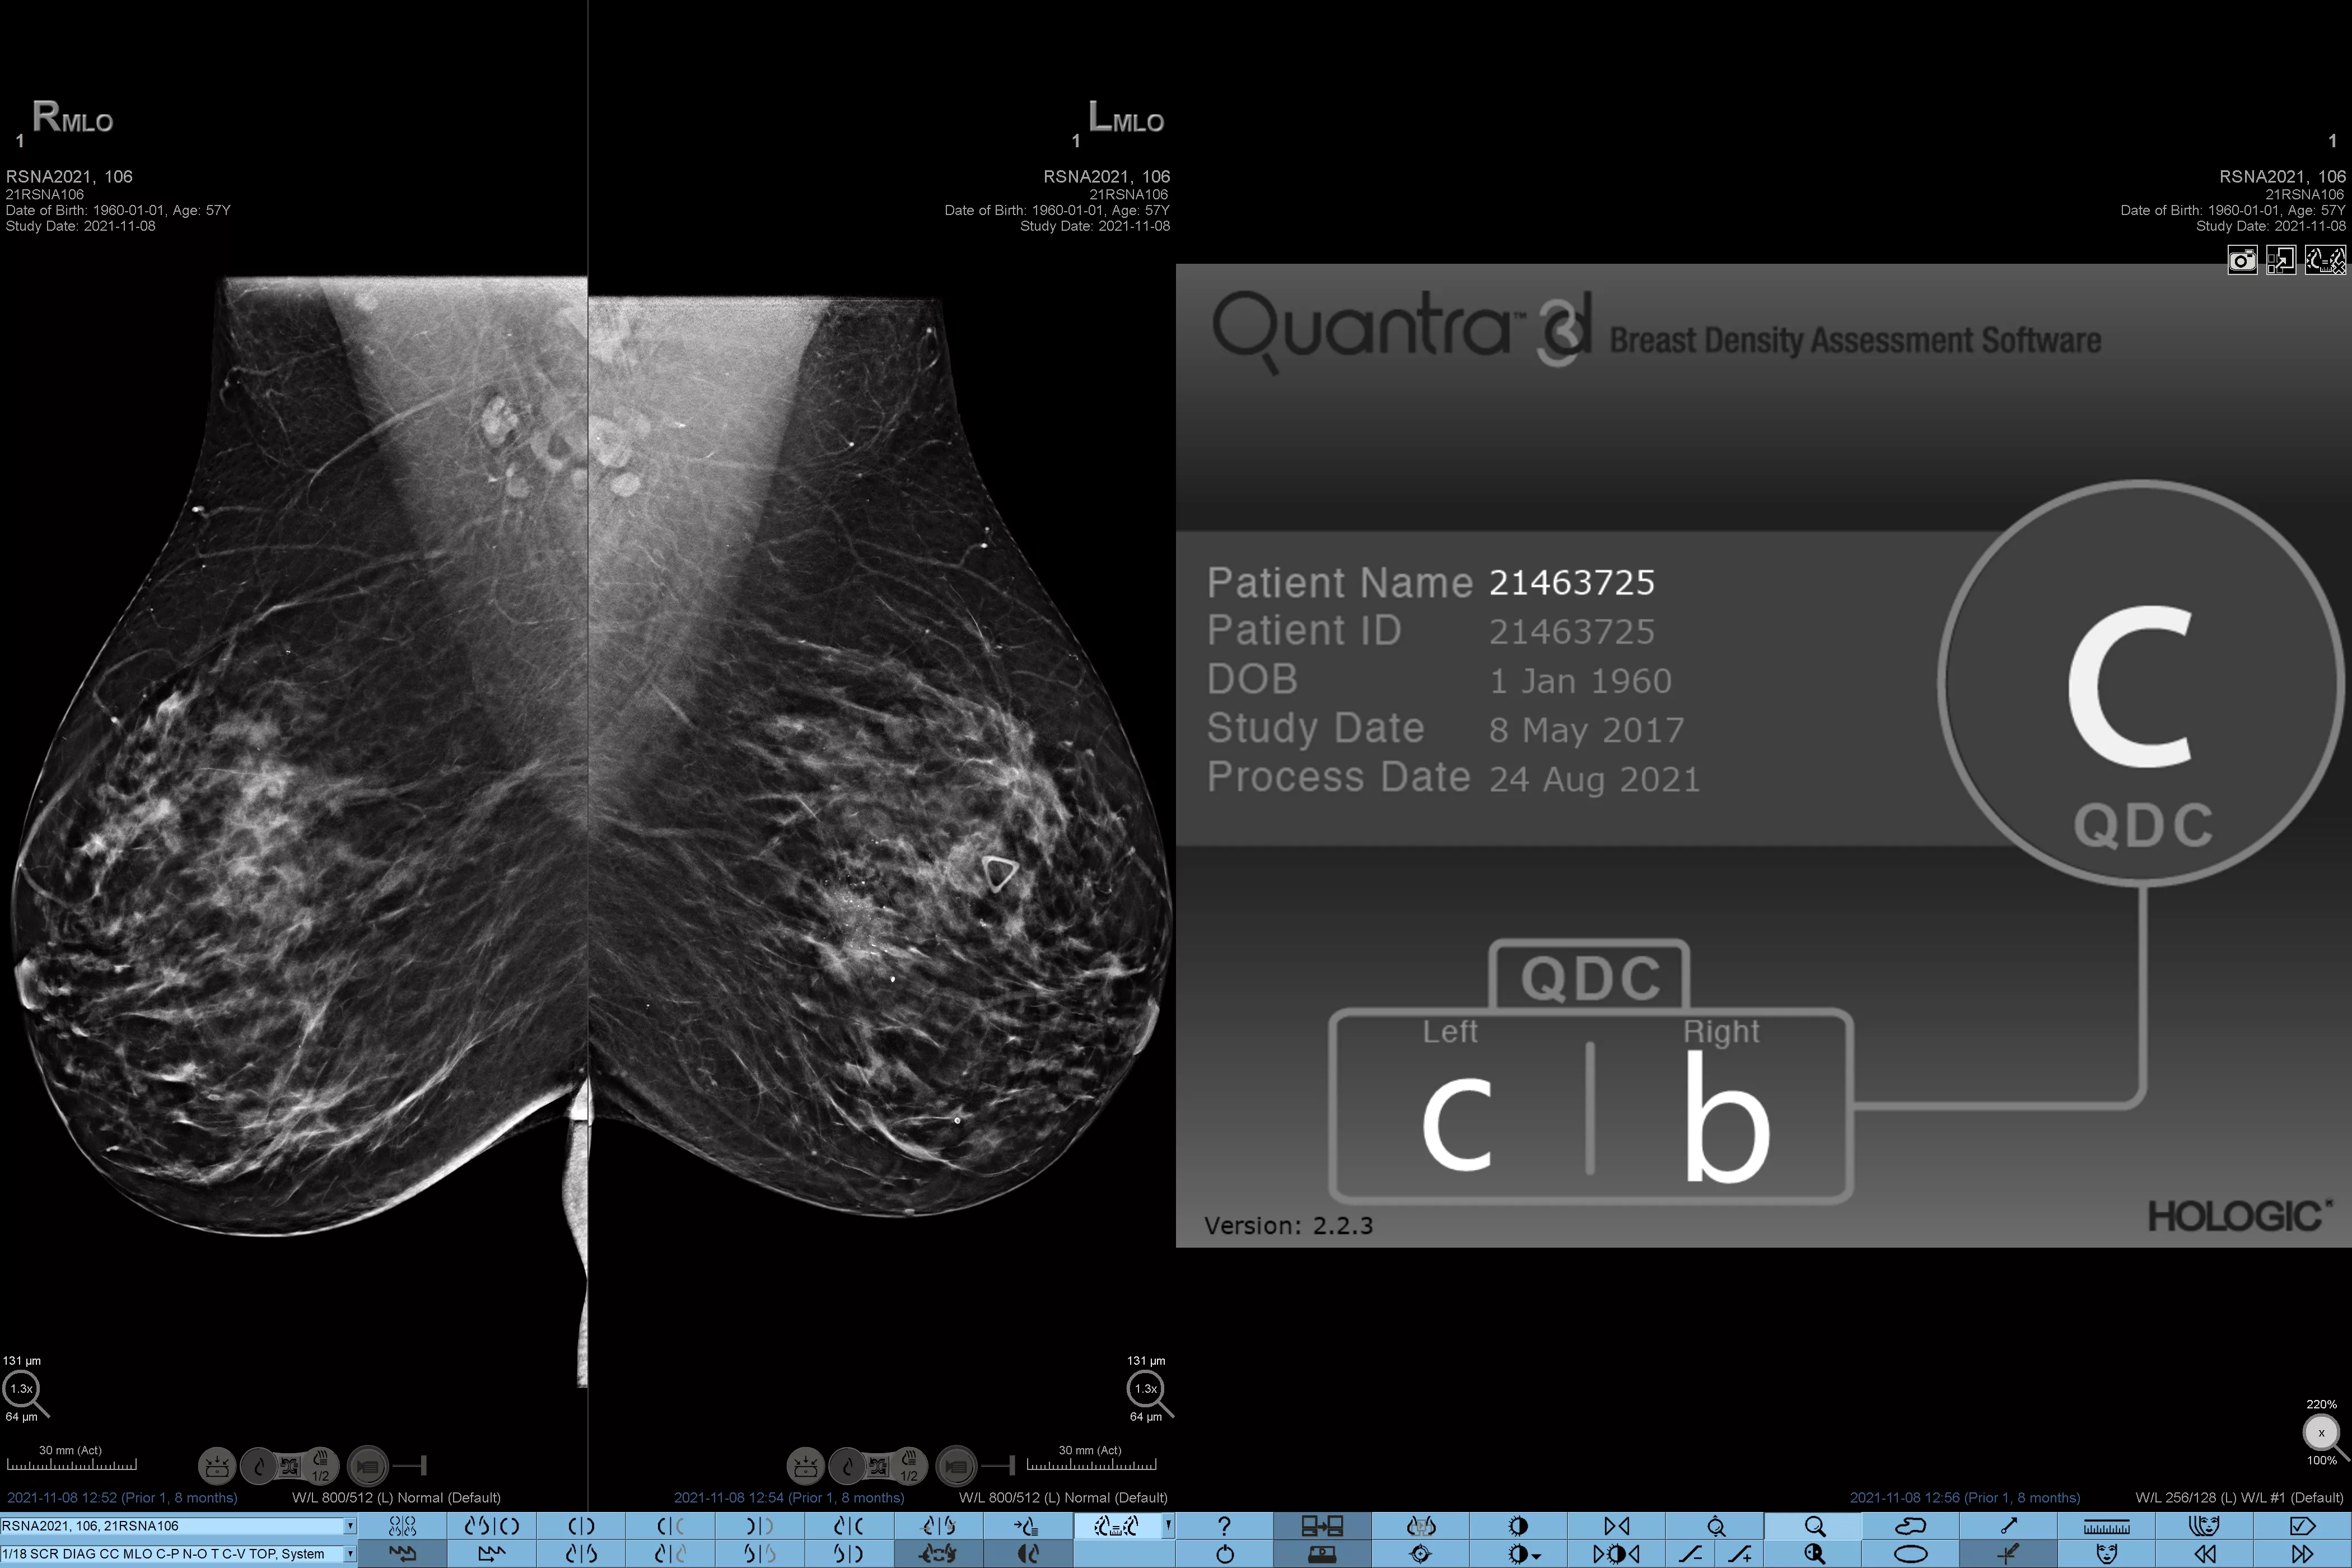

Det är känt att en hög brösttäthet ökar en kvinnas risk för bröstcancer.1 Behovet av noggrann och opartisk analys är därför kritiskt. Med hjälp av maskininlärning analyserar Quantra Technology-programvaran både 2D™- och tomosyntesbilder för fördelning och textur av parenkymal vävnad. Den kategoriserar bröst i fyra bröstkategorier utifrån sammansättning enligt riktlinje från American College of Radiology (ACR) BI-RADS Atlas 5th Edition.2

Objektiv maskininlärningsalgoritm som tilldelar en kategori för brösttäthet baserat på analys av bröstvävnadens textur och mönster.

Den opartiska algoritmen i programvaran analyserar både 2D- och tomosyntesbilder för att:

• Övervinna subjektivitet vid visuell bedömning, vilket ger mer konsekvent och tillförlitlig bedömning*

Riskkategorier8